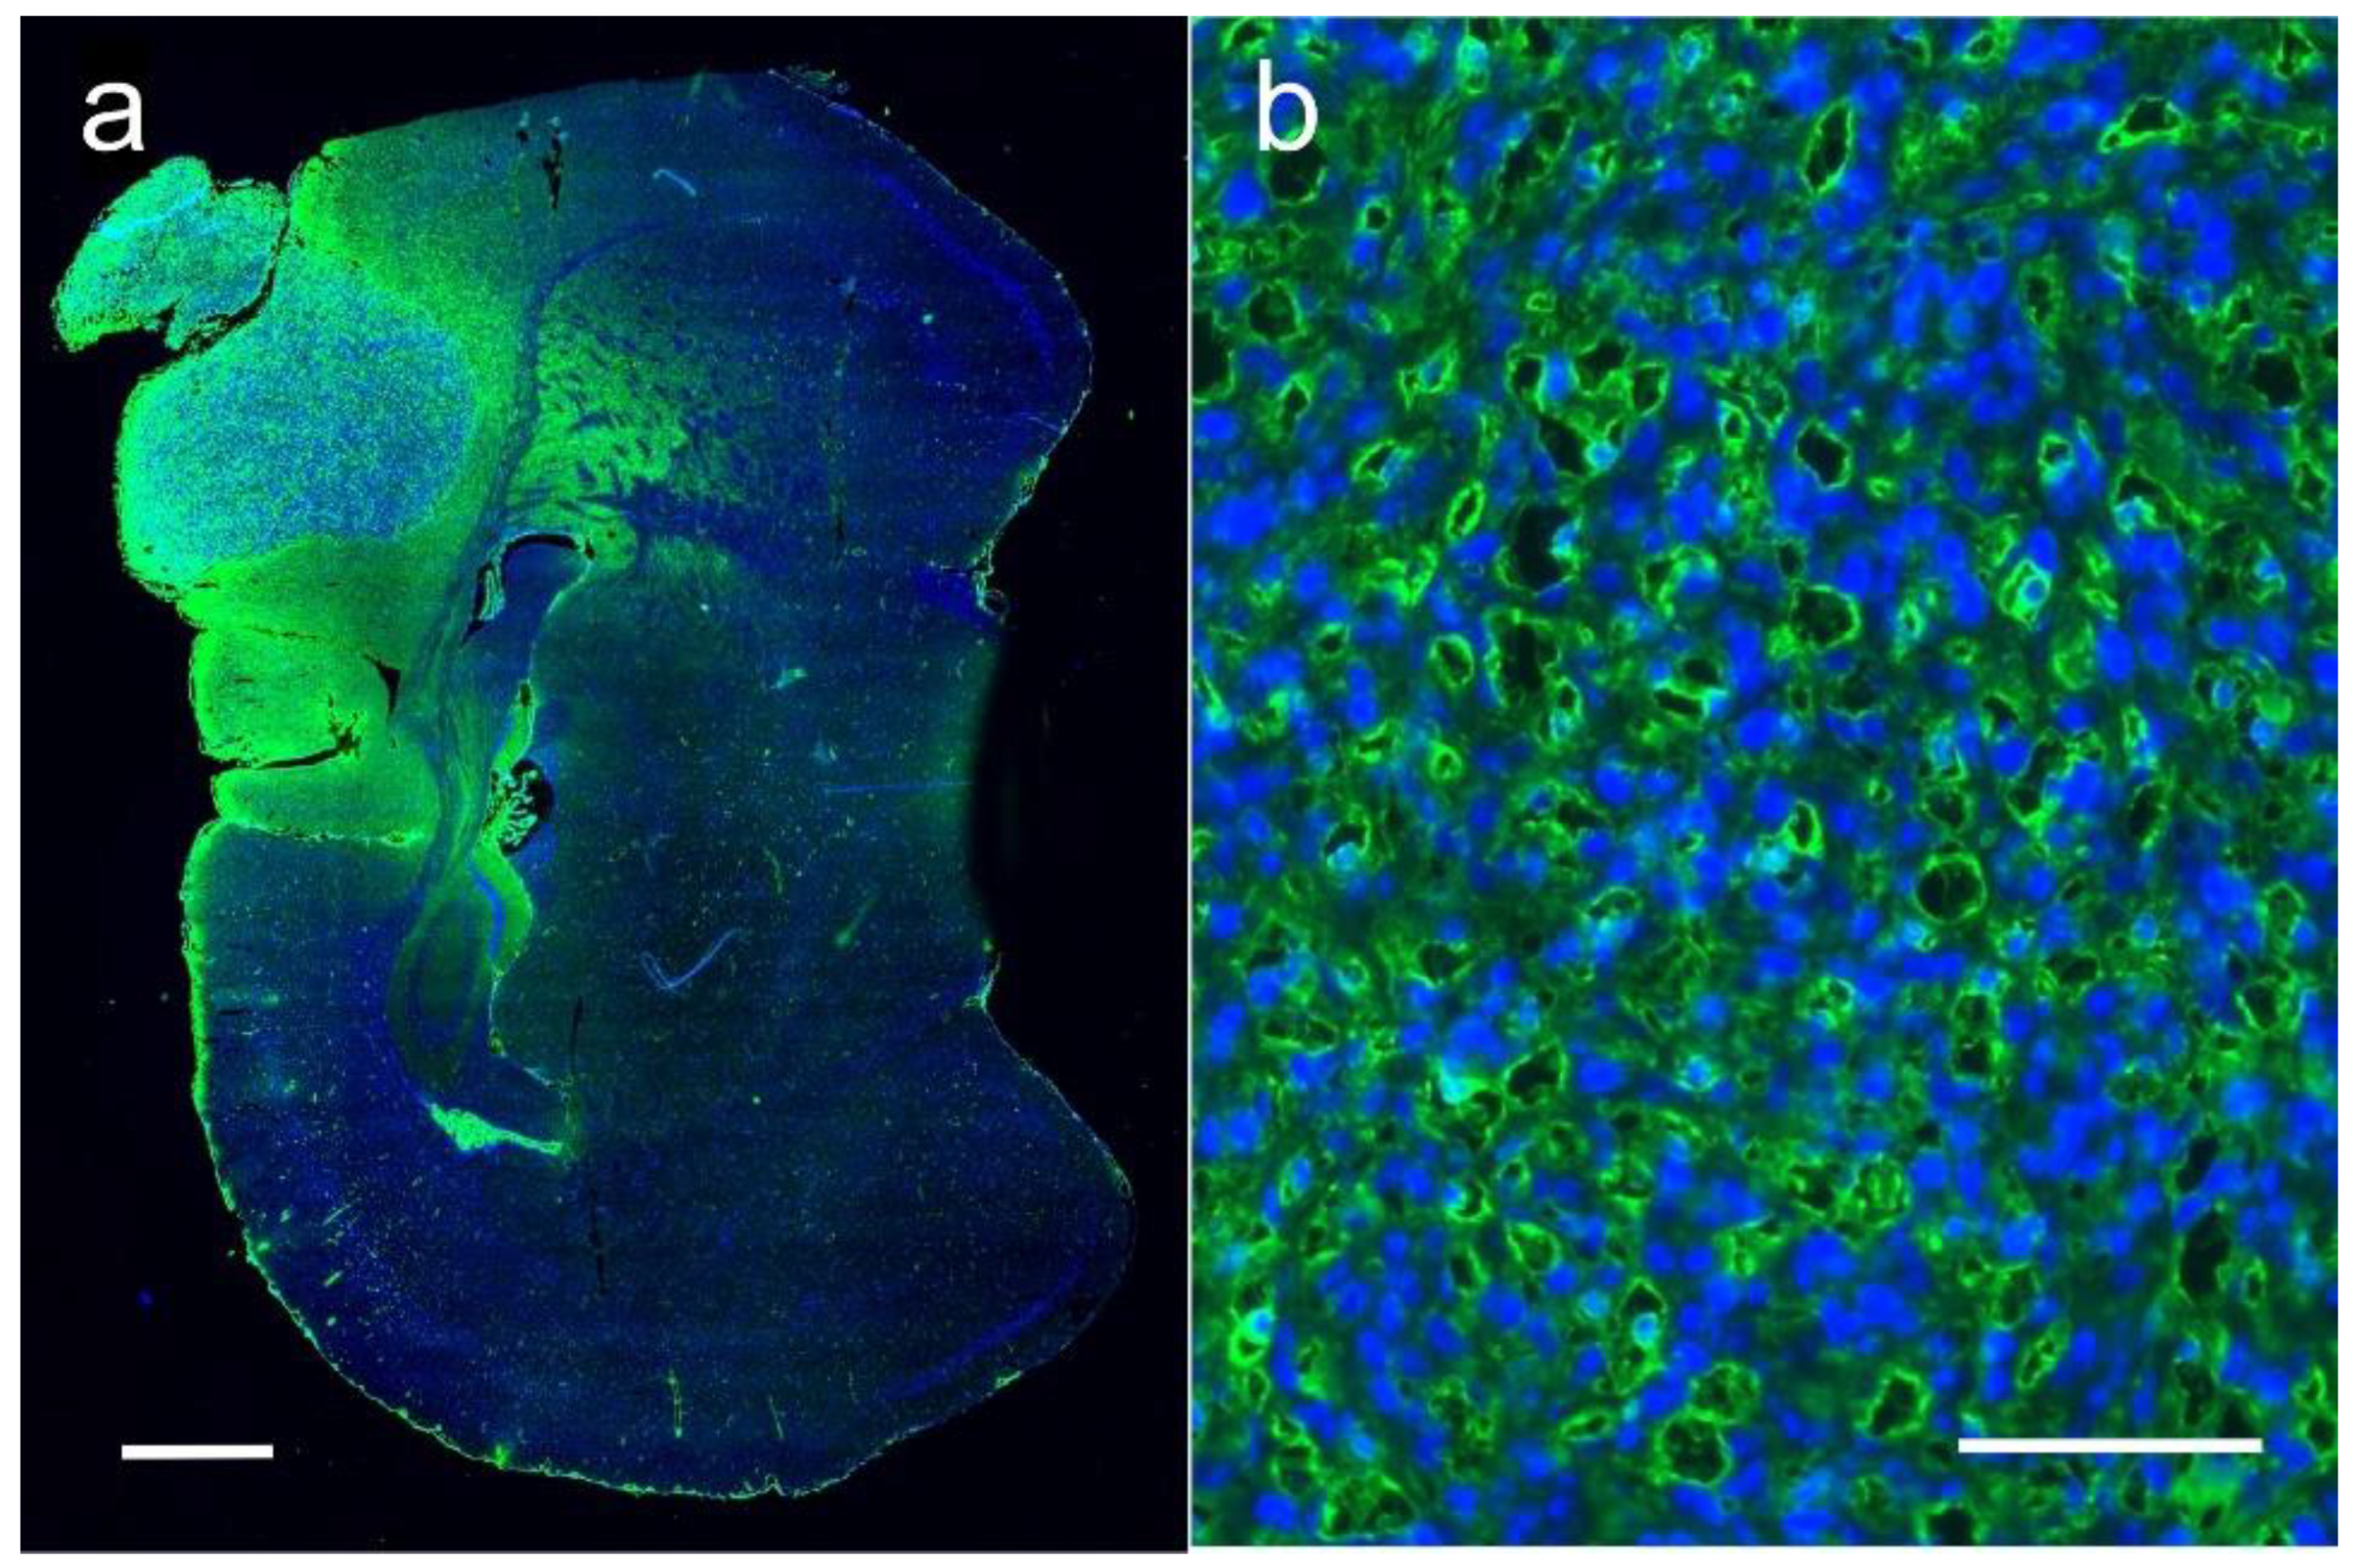

1.5. Iodine Nanoparticle Glioma Therapy

1.6. Iodine Nanoparticle Radiotherapy Synergy with Drugs

1.7. Iodine Nanoparticle Targeting

1.8. Iodine-Enhanced Radiotherapy of Brain Metastases